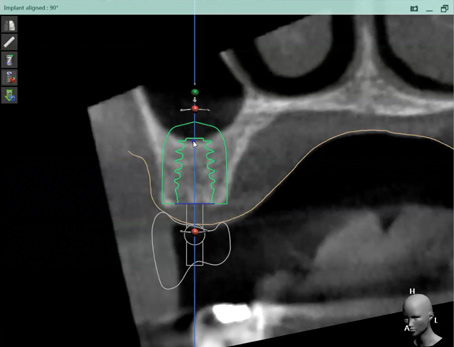

Fig 2. CBCT images: axial (Fig 2) and cross-sectional (Fig 3) views, and 3D reconstruction view (Fig 4) with virtually planned implant Nos. 8 and 9.

Figure 2

Fig 3. CBCT images: axial (Fig 2) and cross-sectional (Fig 3) views, and 3D reconstruction view (Fig 4) with virtually planned implant Nos. 8 and 9.

Figure 3

Fig 4. CBCT images: axial (Fig 2) and cross-sectional (Fig 3) views, and 3D reconstruction view (Fig 4) with virtually planned implant Nos. 8 and 9.

Figure 4

For dental implant-based treatment, the planning phase begins with collection of basic data sets; this is digital touchpoint 1. It includes: (1) a cone-beam CT (CBCT) to view edentulous areas or failing tooth structure, bone, and anatomic landmarks under the soft tissue (Figure 2 through Figure 4); and (2) an intraoral optical scan (IOS) or a scanned model or impression to record the soft tissue and tooth anatomy (Figure 5). The superimposition of the digital imaging and communications in medicine (DICOM) files from the CBCT and the standard tessellation language (STL) files from the IOS allows visualization of how bone, dental structures, and soft tissues relate. Both digital data points are key to implant selection and determining the surrounding bone-grafting needs. An initial treatment plan includes determining the desired implant manufacturer/implant design, size, and positions; these decisions remain the responsibility of the clinician (restoring and surgical team members) and not the technician or planning team.